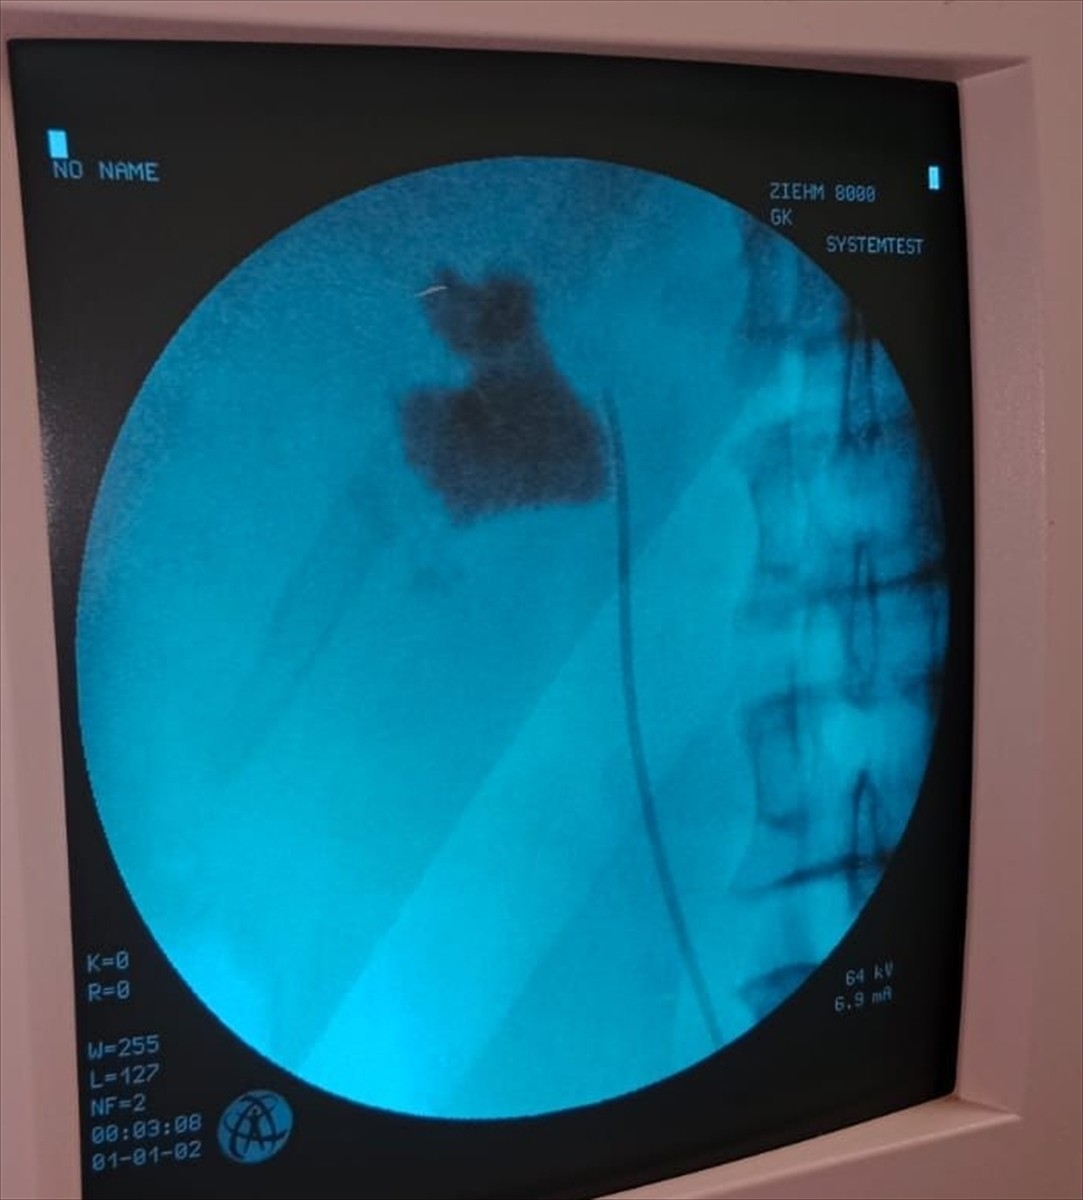

Kırşehir Eğitim ve Araştırma Hastanesi, il genelinde önemli bir başarıya imza attı. Hastaneye başvuran İlhan Çakır isimli hastanın böbreğinde tespit edilen 6 santimetrelik taş, kapalı ameliyat yöntemi ile çıkarıldı.

Üroloji Kliniği'nden Uzm. Dr. Talip Göktaş ve ekibi, hastanın taşını başarılı bir şekilde aldı. Ameliyat sonrası yapılan kontrollerde, hastanın sol böbreğinde taş olduğu belirlenmişti.

Uzm. Dr. Göktaş, hastanın tedavi süreci hakkında şunları söyledi: “Hastamız 1 gün sonra taburcu edildi. Kapalı böbrek taşı yöntemi olan PNL ile ameliyatı başarıyla gerçekleştirdik. Bu yöntem, hastalarımızın açık ameliyatlara göre daha hızlı iyileşmesini sağlıyor.”

Kırşehir Eğitim ve Araştırma Hastanesi'nde 5 yıl içinde 50'den fazla kapalı böbrek taşı ameliyatı başarıyla tamamlandı. Uzm. Dr. Göktaş ve ekibi, bu alandaki deneyimleriyle hastalarına konforlu bir tedavi süreci sunmanın gururunu yaşıyor.